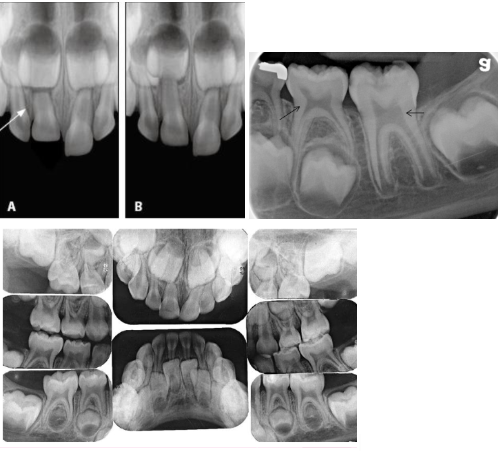

<p><span><strong>How to use the differences in identifying the dentition in </strong></span><strong>radiographs: start with the roots&nbsp;</strong></p>

How to use the differences in identifying the dentition in radiographs: start with the roots

knowt flashcard image

<p><span><strong>How to use the differences in identifying the dentition in </strong></span><strong>radiographs: look at the pulp</strong></p>

How to use the differences in identifying the dentition in radiographs: look at the pulp

Key differences to identify primary vs permanent dentition

 Enamel and dentin are thinner in primary

 Pulp chamber is wider

 Pulp horn is more prominent

 Smaller root trunk for primary

<p><span><strong> Enamel and dentin are thinner in primary </strong></span></p><p><span><strong> Pulp chamber is wider </strong></span></p><p><span><strong> Pulp horn is more prominent </strong></span></p><p><span><strong> Smaller root trunk for primary</strong></span></p>